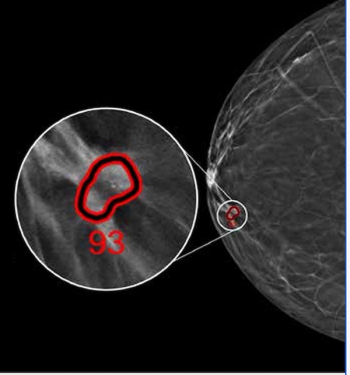

Employing advanced deep learning convolutional neural networks, ProFound Detection Version 4.0 reportedly offers a 50 percent improvement in detecting cancer in dense breasts in comparison to the previous version of the software.